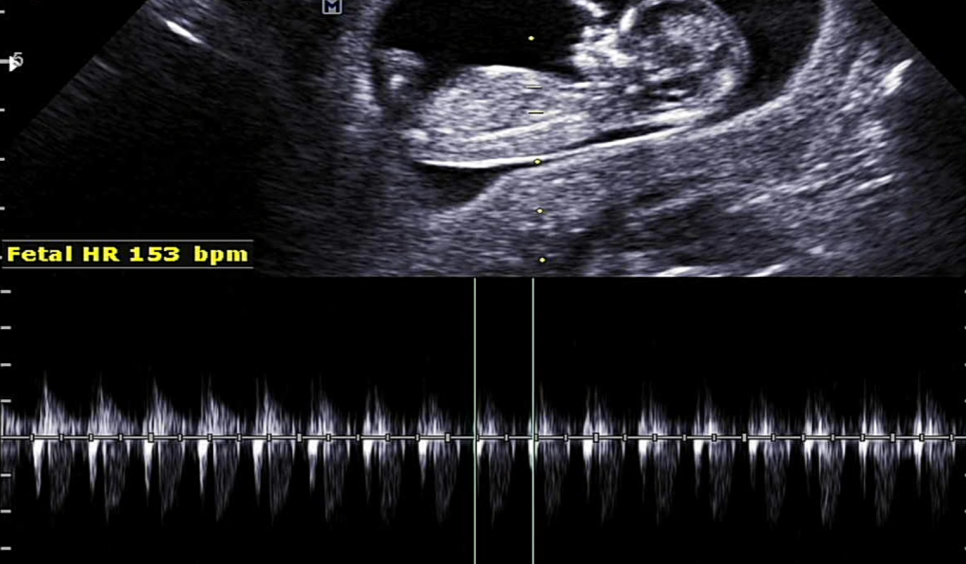

심장 박동도 확인해주시고요153비트가 나왔는데 정상이라고 하더라고요.